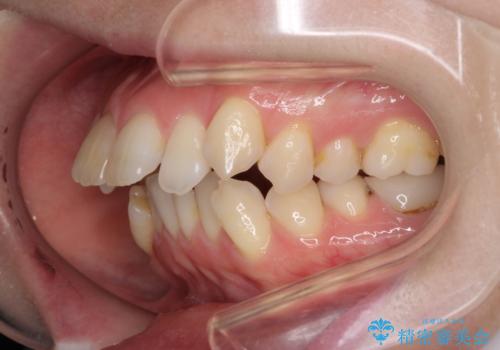

- 上の前歯の飛び出した感じを改善したいとのことで来院された患者様です。

上顎左右第一小臼歯2本、下顎左右第二小臼歯2本を抜歯し、ワイヤー装置にて口元を引っ込めるよう矯正治療を行うこととしました。

上下の前歯に隙間が空くほど上顎前歯が前に飛び出していましたが、抜歯矯正により上下前歯がぴったりと付くほど口元を引っ込めることができました。